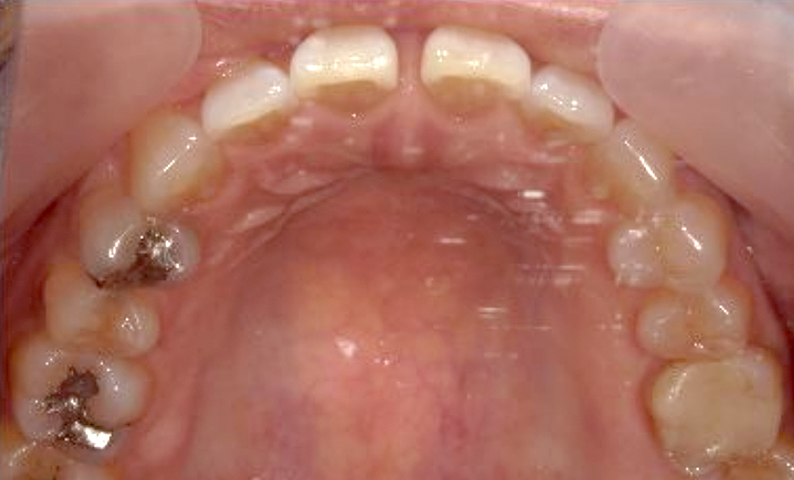

| 治療前 | 治療後 |

|---|---|

|